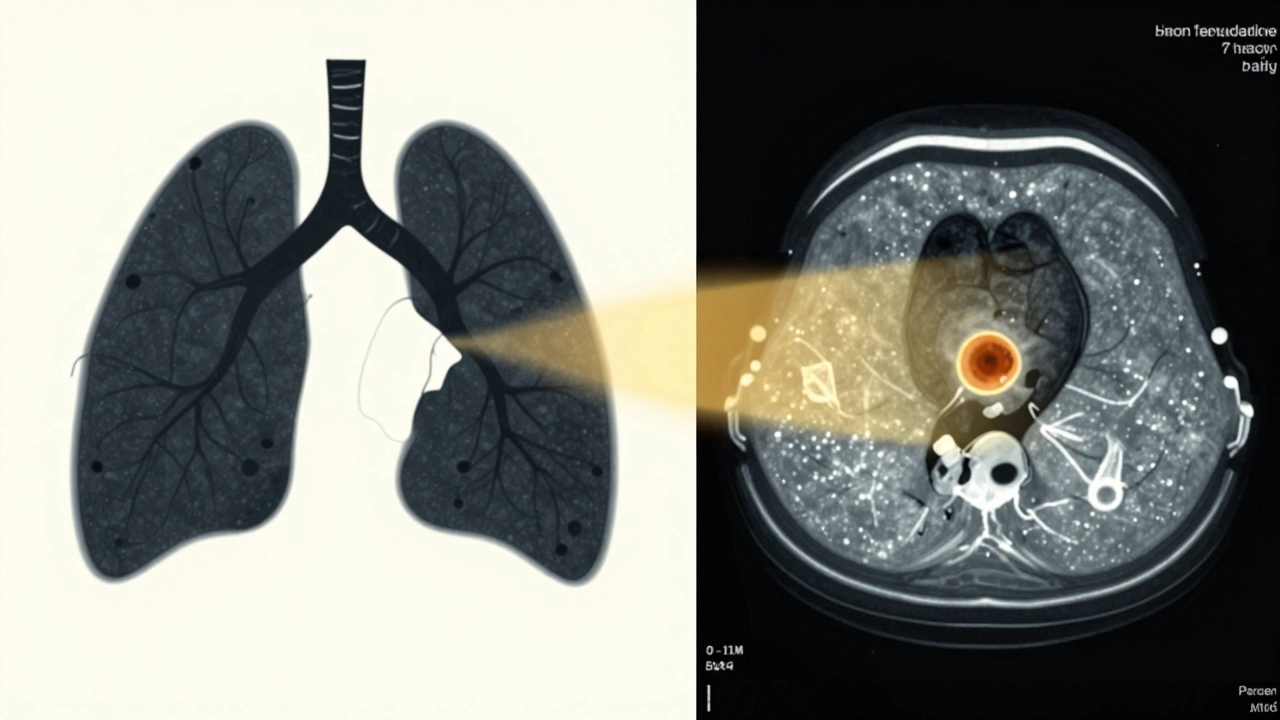

Lung Cancer: Still the Top Cause of Cancer Death

Lung cancer kills more people than breast, prostate, and colorectal cancers combined. The five-year survival rate is about 23%, but that number hides a big gap. If caught early-before it spreads-the survival rate jumps to over 60%. The problem? Only 17% of cases are found at that stage. Most people don’t have symptoms until the cancer is advanced. Smoking is still the biggest risk, but non-smokers get it too, especially women and younger adults. Newer treatments like EGFR inhibitors and ALK blockers have improved outcomes for specific genetic subtypes, but for the majority, chemotherapy and radiation are still the main options. Low-dose CT scans for high-risk smokers have helped, but access remains limited in many parts of the world.

Split image: a smoker coughing on one side, an early lung tumor glowing on a CT scan on the other.